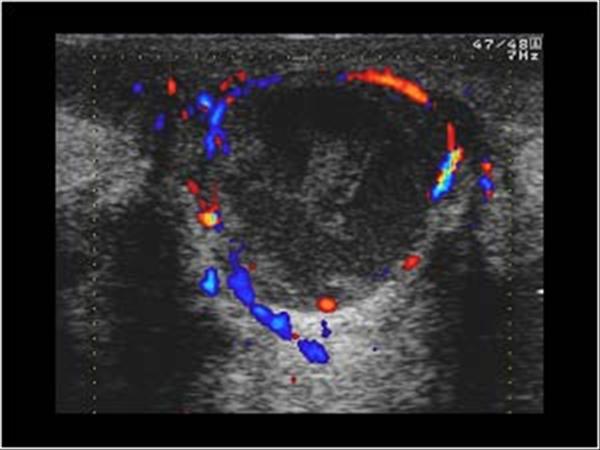

Apxe vú

Apxe vú - Ảnh 3

» Thông tin: Nữ giới – 21 tuổi.

» Lâm sàng: Sưng đau tuyến vú.